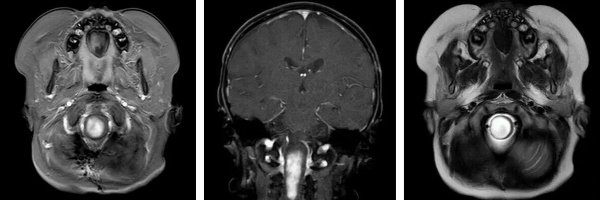

阿什利于3個月前出現(xiàn)頭部歪斜、右上肢無力等癥狀,經(jīng)當(dāng)?shù)蒯t(yī)院MRI檢查發(fā)現(xiàn)延髓及頸髓占位,初步診斷為毛細(xì)胞星形細(xì)胞瘤。盡管在新加坡接受了活檢手術(shù),但由于腫瘤位置極其特殊、手術(shù)風(fēng)險極大,僅完成了少量病理取樣,未能實現(xiàn)有效切除。高達四十余萬元人民幣的醫(yī)療支出并未換來病情的根本好轉(zhuǎn),一家人陷入沉重的經(jīng)濟與精神壓力之中。

術(shù)前影像(MRI)

懷著最后一線希望,阿什利一家跨海越洋,來到我院腦腫瘤科求助。入院時,患兒右側(cè)肢體活動嚴(yán)重受限,面癱癥狀逐漸顯現(xiàn)。影像檢查顯示腫瘤位于腦干中央,與周圍重要神經(jīng)結(jié)構(gòu)和血管關(guān)系密切,手術(shù)難度極大、風(fēng)險極高。